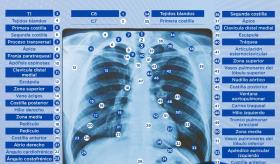

Si bien el cáncer de pulmón no es la enfermedad más común en oncología, tiene una alta tasa de mortalidad en Estados Unidos, incluyendo Puerto Rico.

Puerto Rico actualmente cuenta con tan solo 217 radiólogos, de los cuales, casi la mitad son mayores de 60 años.